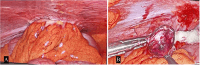

Figure 2

Figure 2. This intraoperative laparoscopic image shows a clear view of the internal abdominal anatomy, focusing on a section of intestines with visible vascular structures on the surface. A small, yellowish lesion or structure is visible near the center (A), possibly indicative of a pathological finding such as omental fat necrosis (gangrenous appendices epiploica) (B).